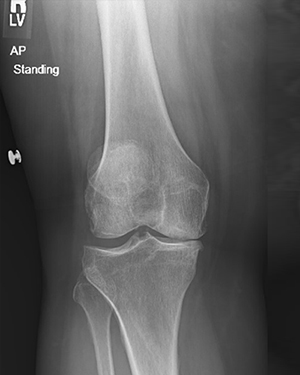

Revision Knee Joint Replacement- Two Weeks after Surgery

Ms. D. Z, is 2 weeks from Right knee replacement and 2 months from Left knee replacement.

This is Ms. D. Z, she is 2 weeks from Right knee replacement and 2 months from Left knee replacement. She is walking well with just a cane at 2 weeks post op.